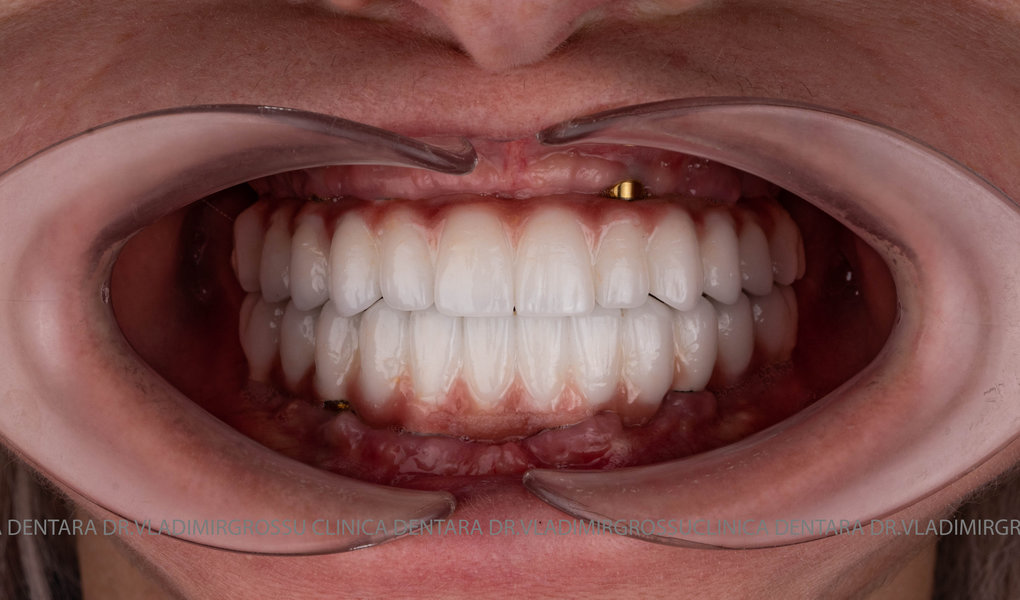

Cazuri clinice conceptul All-on-6